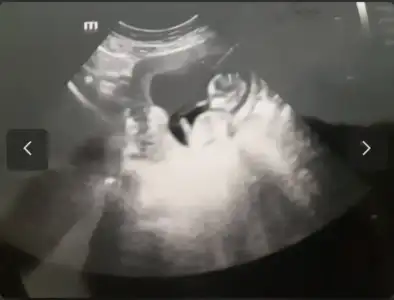

karından sanırım? prenses gibi8 haftalık burda güzel teyzeleri çok merak ediyorum bana da yorum yapın annem 3 sene tüp bebek deneyip bana hamile kaldı şimdi cinsiyetimi öğrenip hasırlık yapmak istiyor

karındansa prenses gibi8 haftalık burda güzel teyzeleri çok merak ediyorum bana da yorum yapın annem 3 sene tüp bebek deneyip bana hamile kaldı şimdi cinsiyetimi öğrenip hasırlık yapmak istiyor